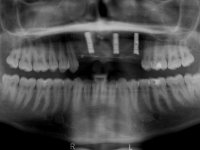

Foi aconselhada a extracção dos dentes 12 e 11 e esperar mais 3 meses para se conseguir uma completa cicatrização da zona. Estabilizada a situação fazer-se –ia um enceramento de diagnóstico que dando origem a uma guia imagiológica permitiria fazer uma TAC. em que o posicionamento idealizado dos dentes pudesse ser relacionado com o património ósseo. O objectivo seria fazer uma ponte cerâmica implanto suportada.

O paciente foi observado conjuntamente e a dúvida que surgiu de imediato foi se seria possível com a regeneração óssea a efectuar poder ser reabilitada naturalmente a zona das papilas interdentárias. Nesse sentido foi feito um enceramento de diagnóstico que contemplaria as duas hipóteses, utilizando ou não a cerâmica gengival. A confecção desse enceramento foi fundamental para expor ao paciente a dificuldade da reabilitação. O wax-up deu origem a um mock-up que foi aprovado pelo paciente e que simultaneamente serviu de guia imagiológica. O caso foi planificado cirurgicamente e realizada uma guia cirúrgica com que foram colocados os implantes. Após 10 semanas foi feita a 1ª impressão para confecção da ponte provisória. Foram criados os primeiros perfis de emergência na gengiva artificial e foi digitalizado o modelo. Por processo de CAD-CAM foi confeccionada uma ponte provisória aparafusada baseada no enceramento de diagnóstico. A ponte trabalhou durante 8 semanas os tecidos moles que foram fielmente copiados numa impressão com técnica de moldeira aberta. Os transferes foram individualizados com resina composta para copiarem fielmente os perfis de emergência criados pela ponte provisória. Confeccionado o modelo de trabalho definitivo, foi realizada uma infra-estrutura em zircónio seguindo a orientação do enceramento de diagnóstico. O assentamento da infra-estrutura foi testado em boca e simultaneamente foi novamente impressionados os tecidos moles com um silicone fluido. Nessa consulta foi feito o levantamento da cor. Os dentes 13 e 23 apresentavam uma saturação anormalmente forte que resolvemos não valorizar, optando por privilegiar a relação com o sector antero-inferior. Foi realizada uma nova gengiva artificial com a impressão que acompanhou a impressão de arrasto com a infra-estrutura. Após a colocação da cerâmica na infra-estrutura foram coladas as meso-estruturas. O trabalho final foi aparafusado lentamente permitindo a adaptação dos tecidos moles.